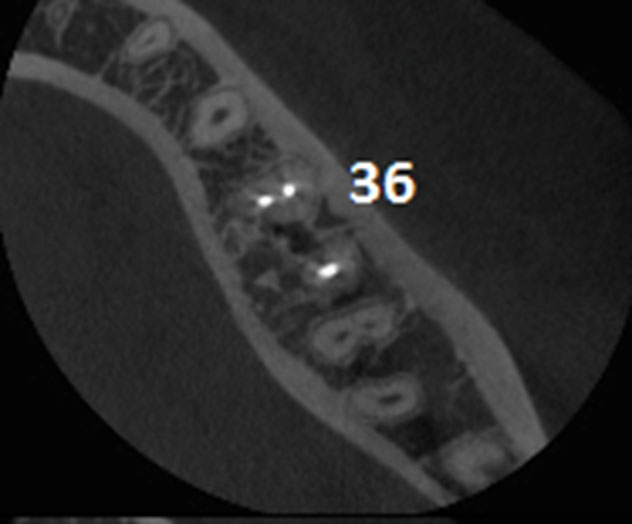

Age of patient: 15 years

Tooth: left mandibular first molar. Poor restorative prognosis. Very large lesion.

Work done: Obturation done after multiple calcium hydroxide dressings over 5 months and seeing lesion decrease in size. Fiber-post placed in distal canal. Core build-up done with Luxacore composite. Adv crown.

Notes: This is endo done for a “holding period” for implants later on. Healing of bone ensures a more favorable environment for implant placement.

Pre-op

Pre-op CBCT

Obturation done after 5 months of calcium hydroxide

May 2015 – 3 year recall

3 year recall CBCT

Pre-op & 3 year recall